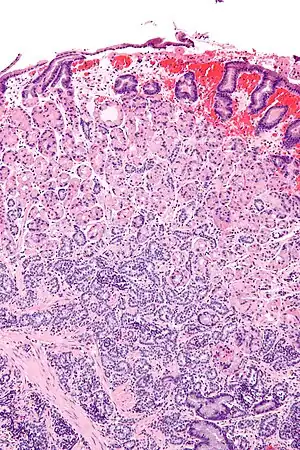

Gastrinoma

Um gastrinoma é um tumor do pâncreas (aproximadamente em 1/3 dos casos) ou extrapancreático (principalmente na parede duodenal) que segrega gastrina em excesso, o que provoca ulceração no duodeno, estômago e intestino delgado.[1]